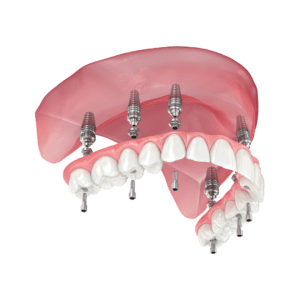

The implant process typically takes several months from the initial consultation to the final placement of the crown. However, every case is unique.

Yes, dental implants have been used safely for over 50 years and have a success rate of over 95%. Our clinic uses the latest technology and follows strict safety protocols to ensure the best outcomes.

Dental implants have a success rate of over 95%, making them one of the most reliable tooth replacement options available.